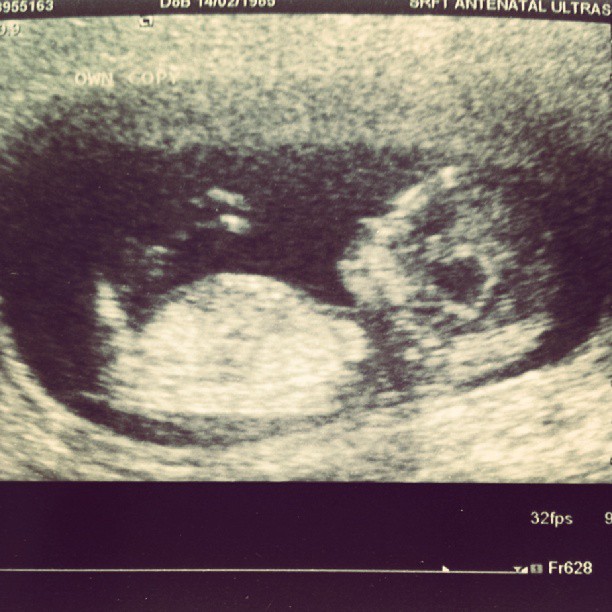

Not even sure you could tell from this pic but would love to know what people think?? Girl or boy?? :-/

I dont think i see a nub.

Not a great image for nub guessing, do you have any others?